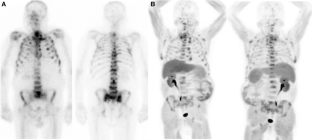

Fig. 2